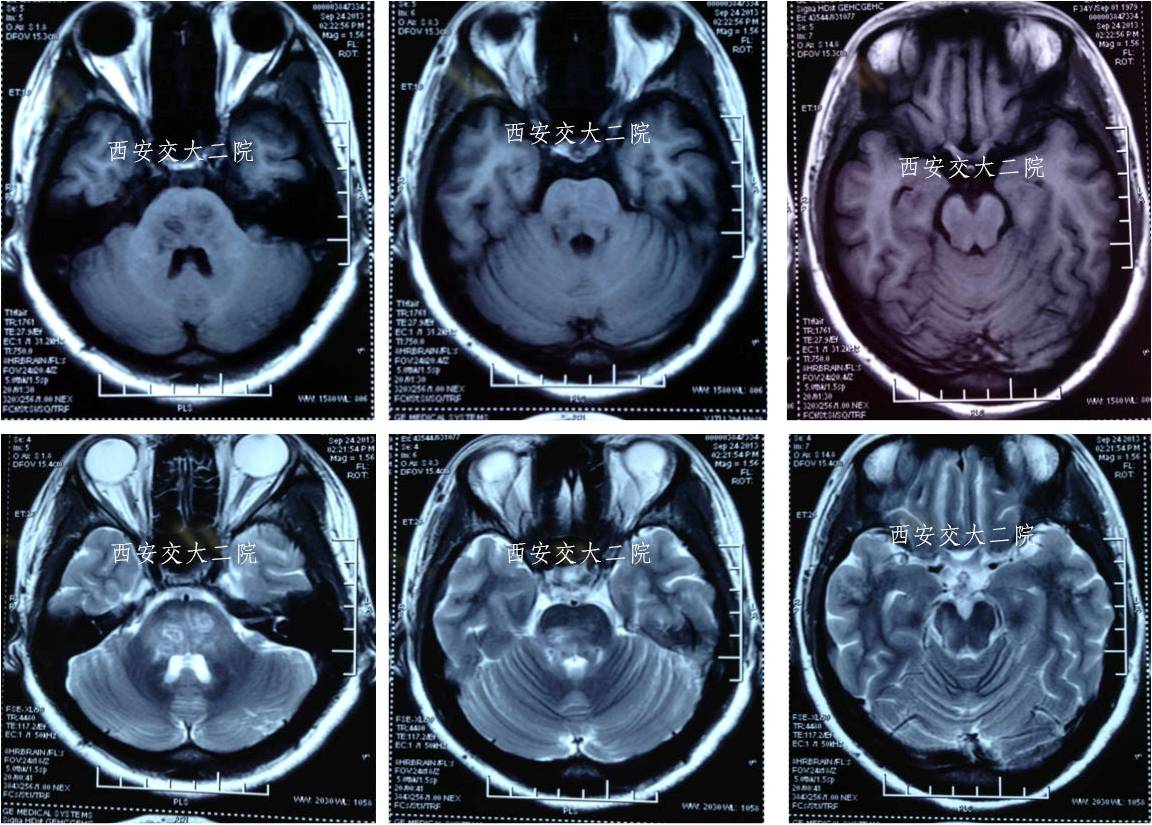

术后10天MR

术后2月随访

mRS评分1;

行走时右下肢稍拖曳;

言语、颅神经及书写完全正常。

术后3月完全恢复正常

术后2年随访(至2015年9月23日)患者完全正常。病情无复发。